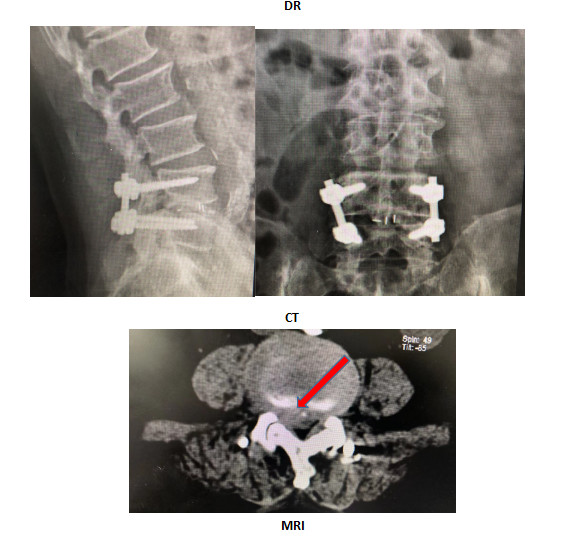

患者2年前因“腰椎间盘突出症”于当地医院行腰椎后路融合内固定手术(L4/5),术后效果可,2月前无明显诱因出现腰部及下肢疼痛,查体:右下肢直腿抬高试验阳性(50°),L3/4右侧椎旁压痛、叩击痛阳性,伴放射痛。后于我院行椎间孔镜手术(L3/4),术后恢复可。

术前影像: